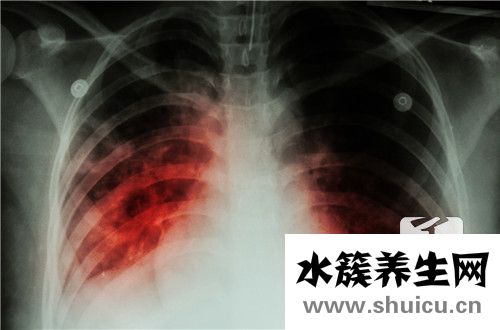

肺是非常重要的人體器官。 它可以包含通風,吸入,調節吸入,還可以促進肺部血液循環系統。 當您感覺略微呼吸不暢,并且肺部感到不適時,大多數人選擇去醫院的門診進行檢查。 如果他們被診斷出肺密度低和...